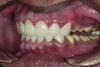

Figure 2. Preoperative 1:2 retracted frontal view.

Figure 2

A thorough clinical examination and analysis were carried out to assess the esthetic and functional problems of the patient (Figure 2 through Figure 7). The medical history was non-contributory, except for mild leukoderma. Temporomandibular joint (TMJ) function was within normal range.